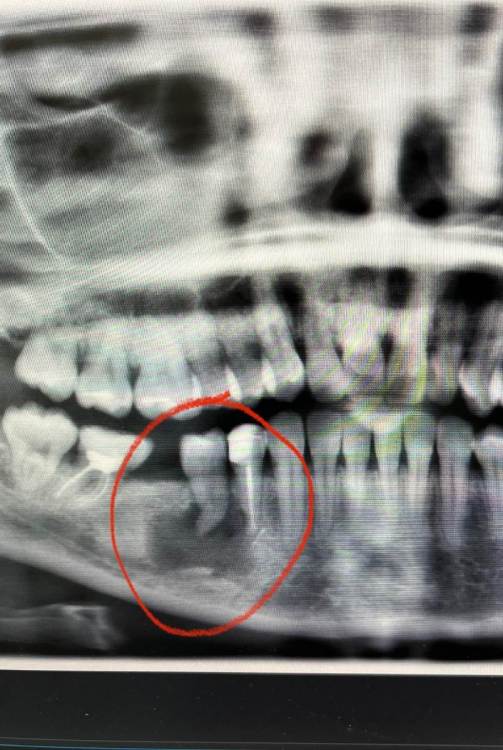

Здравствуйте,вчера была у стоматолога по одному зубу а увидели ппц.Что с этой кистой делать?на сколько это страшно и куда обращаться теперь?Возможно ли её убрать без удаления Зубов??